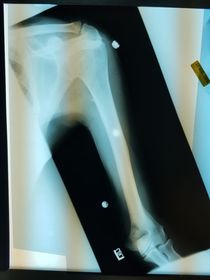

Which projection/position is this? PA Lateral Humerus

Which projection/position is this? AP External Humerus ________________________ Epicondyles are parallel to IR

Projection/position? Lateral Humerus